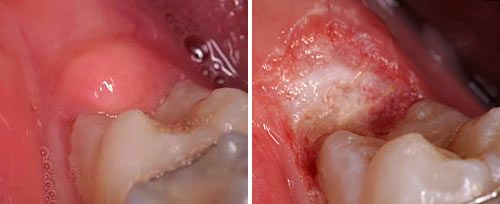

软组织切除

软组织切除:用激光逐层剥离软组织,直到到达所需深度,侵入性更低,操作更精准。激光的凝血效果也可避免形成血肿,也适用于去除肉芽、息肉和囊肿等。

口腔激光怎么治疗口腔特色诊疗——激光治疗_https://www.jmylbn.com_新闻资讯_第9张

激光纤维瘤切除前后对比图

口腔激光怎么治疗口腔特色诊疗——激光治疗_https://www.jmylbn.com_新闻资讯_第10张

激光智齿远中盲袋切除前后对比图